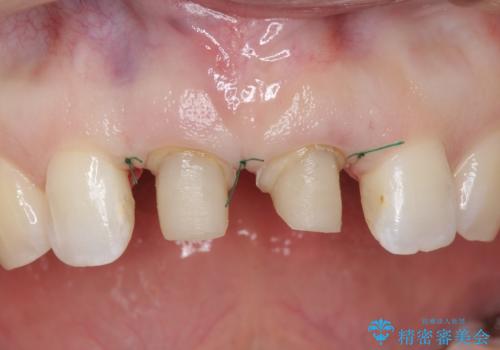

前歯を下げるために、上下左右の小臼歯を抜歯することになりましたが、すでに前歯の角度を不自然に作ってあるため、

もう一度前歯を元の角度に被せ直してから仮歯で矯正を行いました。

その後、マージンが舌側が深い状態だったため、歯ぐきの手術(歯周外科処置:APF)を行ってから最終的なセラミックを装着しました。

治療途中